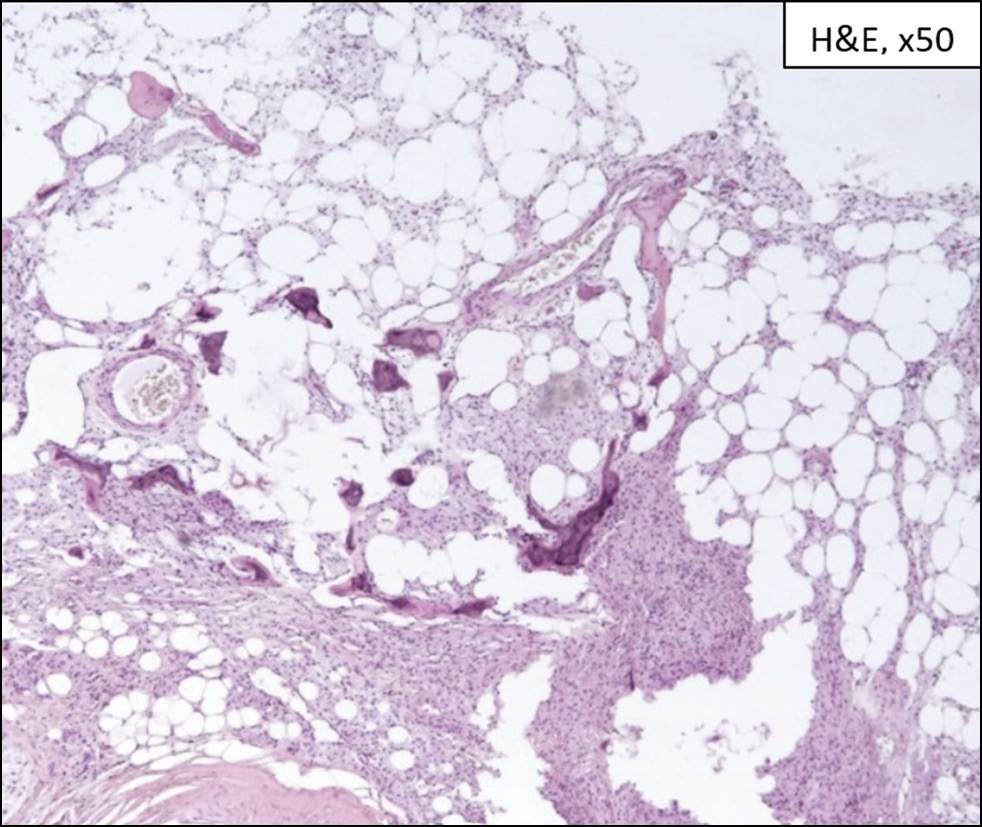

При гистологическом исследовании в опытной группе клетки Гоше занимали от 10 до 90% (медиана — 30%) площади костномозговых полостей. Очаговые некробиотические изменения клеток Гоше на разных участках инфильтрата встречали во всех исследуемых случаях, в двух случаях определяли обширные поля некроза клеток Гоше. В 13% случаев определяли поля отёка «опустошённой» стромы костного мозга, наиболее вероятно — реактивные изменения, расположенные перифокально по отношению к участкам некроза. Во всех случаях выявляли мозаичный грубоволокнистый фиброз стромы костного мозга, преимущественно с вовлечением периваскулярных областей. В 87% случаев определяли признаки реактивной перестройки костных балок с участками активации надкостницы и фокусами остеокластической резорбции. При слепом методе исследования не прослеживалось зависимости сочетания и степени выраженности обнаруженных особенностей морфологической картины, равно как и площади костномозговых полостей, занимаемой клетками Гоше, от наличия и длительности проводимой ЗФТ (рис. 7, 8а, 9а).

Рис. 7. Микрофотограмма гистологического препарата спонгиозной кости головки бедра пациента с болезнью Гоше, окраска гематоксилином и эозином, ув. ×50. Видна очагово-интерстициальная инфильтрация костного мозга клетками Гоше с фокусами перестройки костных балок и мозаичным периваскулярным склерозом.

Fig. 7. Microphotogram of histological preparation of the spongy bone of the femoral head in patient with Gaucher disease, stained with hematoxylin and eosin, ×50. Focal interstitial infiltration of bone marrow by Gaucher cells with foci of bone girder reconstruction and mosaic perivascular sclerosis is visible.